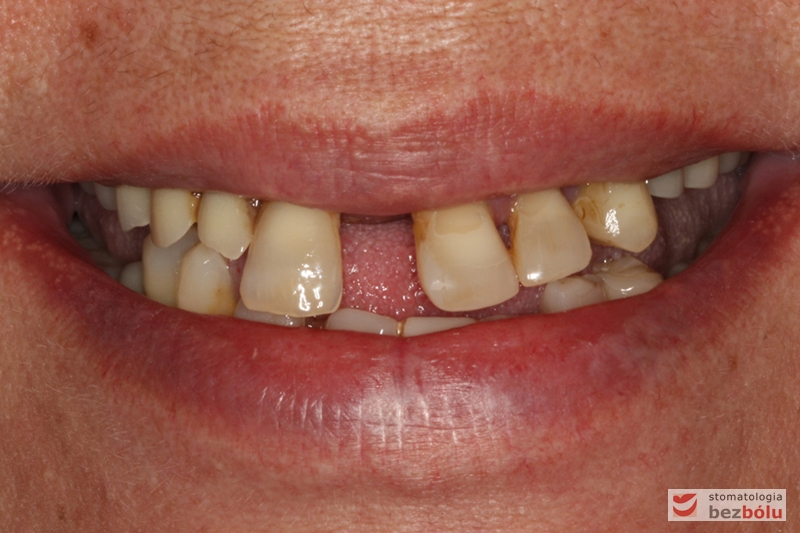

Stan wyjściowy - bez protez, liczne braki zębowe i po 2 nierokujące zęby w szczęce i żuchwie

Stan wyjściowy – bez protez, liczne braki zębowe i po 2 nierokujące zęby w szczęce i żuchwie